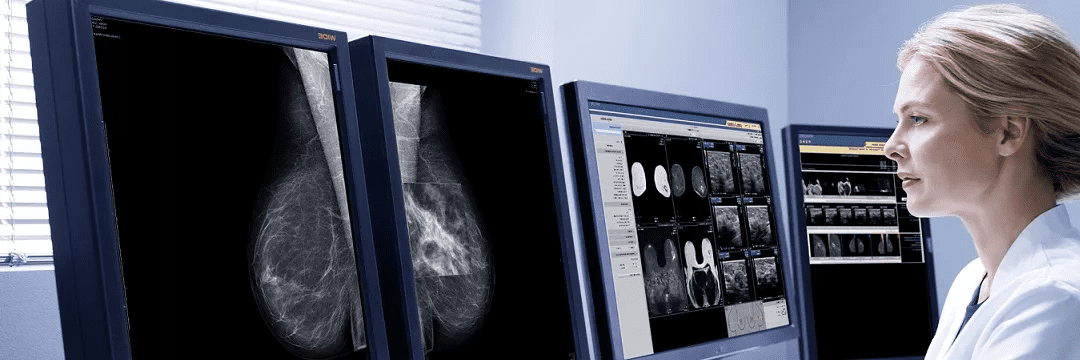

“Insight Medical Imaging” предоставляет полный спектр услуг диагностики различных заболеваний груди, включая ультразвуковое исследование, ядерную медицину, МРТ и биопсию. Все услуги, предоставляемые клиникой, полностью аккредитованы Канадской ассоциацией радиологии и Обществом радиологов Альберты.

Клиника работает пять дней в неделю (с понедельника по пятницу). Во всех заведениях скрининга молочной железы работают настоящие профессионалы. Если после обследования вам рекомендуют дополнительные обследования или анализы, можно быстро сделать их в тот же день без необходимости согласования повторного обследования. Это уменьшает дополнительный стресс для пациентов и позволяет ускорить лечение. В клинике все сделано для того, чтобы обследование и лечение были комфортными. Здесь есть отдельная зона ожидания с удобными сиденьями, баром и напитками. Персонал клиники очень вежлив и готов всегда помочь.

Пройти маммографию можно также в центре «Medical Imaging». Это самый большой радиологический центр Альберты. Здесь работает более 100 радиологов с разными специализациями, а также более 450 технологов и вспомогательного персонала. Центр работает с 1996 года.

Дискомфорт исчезнет сразу после завершения процедуры. После того, как процедура завершится, полный отчет будет направлен врачу, который вас направил на обследование.